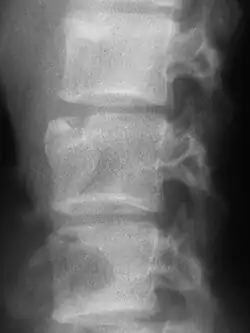

Die Schmerzen sind uncharakteristisch und können als banaler Rücken- oder Kreuzschmerz verkannt werden. Im frühen Stadium kann die Röntgenuntersuchung ohne Befund sein. Ist der Prozess gut abgekapselt, zeigen auch die Laborwerte keine Auffälligkeiten. Ein gutes Hilfsmittel ist hier die Szintigraphie, mit der sich die Aktivierung des Knochenstoffwechsels nachweisen lässt. Das MRT zeigt den entzündlichen Vorgang im Knochen und in den umgebenden Weichteilen.

Die tuberkulöse Spondylitis ist als Sonderfall zu sehen. Bei langsamem Verlauf kommt es, mit relativ geringer Symptomatik und manchmal wenig auffälligen Laborwerten, zu einer allmählichen Zerstörung eines oder mehrerer Wirbel („Wirbelkaries“).